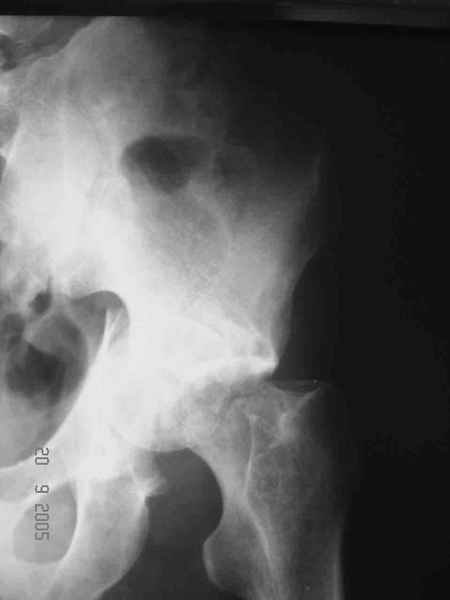

Привет! Вот недавно прооперировали похожий на ваш случай - впадина + шейка (правда у нас впадина поперечный+задний край). После травмы прошло 4 недели. мужчине 46 лет. С такой комбинацией все показания к первичному протезированию. Морально и технически мы к этому уже созрели.Но больной не собрал денег на протез. Выполнили остеосинтез впадины и шейки, прекрасно понимая, что головка вскоре рассосется, мы хотя бы надемся что к этому времени таз срастется, как говорится создали все условия для дальнейшего протезирования (может, и протез в последующем подешевле будет, в смысле, без укрепляющего кольца?). Привет Рункову!

Привет Алекей! Сделано неплохо, поздравляю, хотя второй винтик можно было бы и подлиннее в шейку загнать! Пара вопроов: доступ такой же? головка была свободной или висела на капсуле?

Отправитель: Алексей Смирнов 27 Сентябрь 2005, 22:35

Согласен, можно было и подлиннее. Доступ такой же - чрезвертельный, только разрез кожи прямой (а не Y, чего то я разницы не ощущаю). Головка была абсолютно свободной (то есть во время остеосинтеза таза лежала в стакане и не мешалась). Шансов, что она прирастет 0,00001%. Хотели даже выбросить, но привинтили как временный биологический протез (читай свободный трансплантат), чтоб на период срастания таза бедро проксимально не ушло (может ортопеды потом спасибо скажут). Ну а у вас первичное протезирование при переломе впадины тоже пока полько в планах?